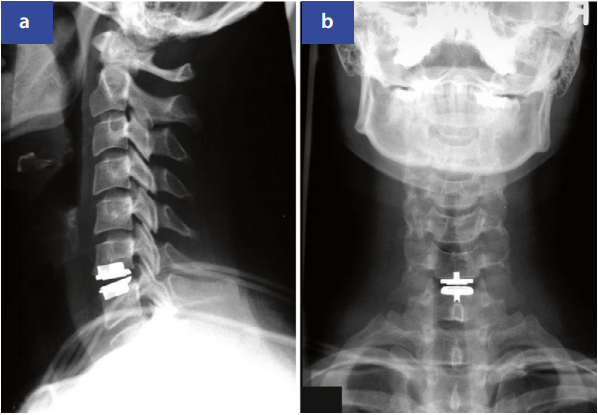

手术治疗相对适应证:保守治疗6周无效的持续性疼痛(缩短病程)。绝对适应证:显著运动障碍或脊髓损害。术式包括前路显微椎间盘切除+融合术或人工椎间盘置换(图3)、后路椎间孔切开术等。单纯椎间盘切除术后2年易出现节段后凸和不稳。

图3:C6/C7髓核切除术后状态及椎间盘假体植入术,侧位(a)与前后位(b)X线影像